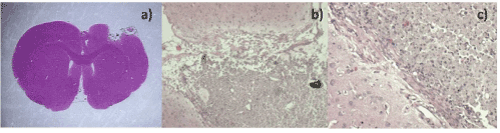

| Figure 13: a)Cerebral cut of post-treatment tumor with MTX/SiO2 (3 months). We observe the lesion site with an area of necrosis, mild inflammatory response, nanostructured material conglomeration (calcified aspect), without evidence of neoplastic cells; b) and c) Cerebral cut after treatment with MTX/SiO2 (6 months) showing mild inflammation with abundant macrophages and nanomaterial (calcified aspect) without tumor cells. |